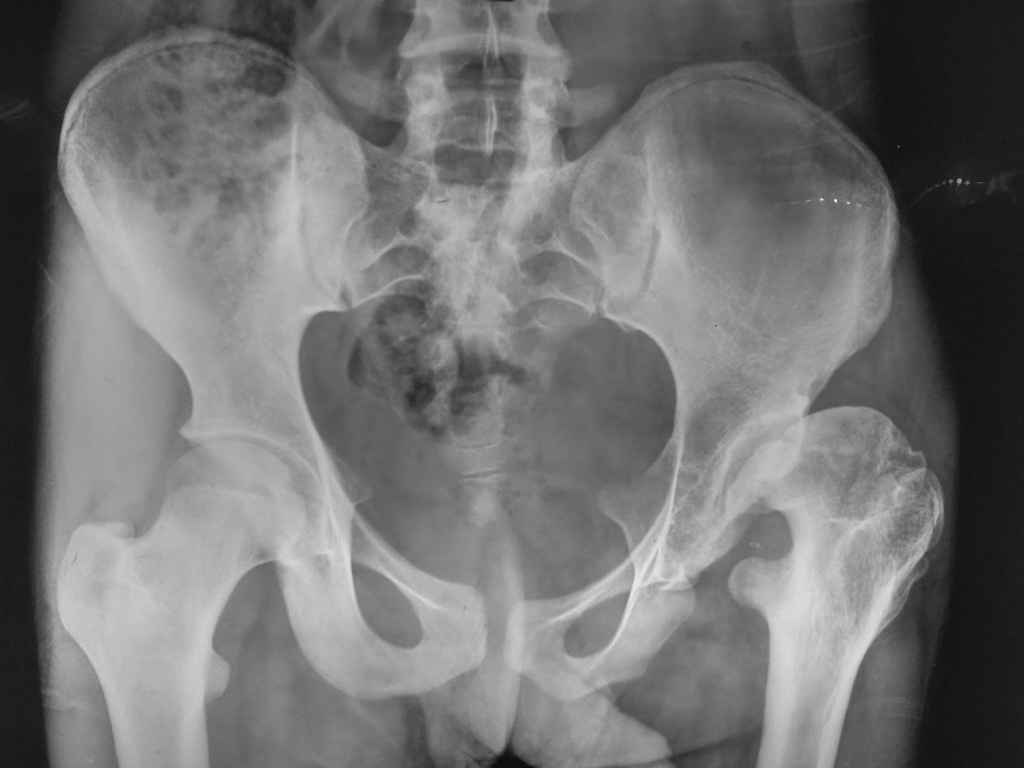

Acetabular displasia

Patients Age 17 years.LLD 3 inches,

Unable to squat and sit cross leg.Flexion at hip 90 deg, abduction adduction 5-10 degree.

evolution of this hip is to a degenerative arthritis. I suggest periacetabular osteotomy to provide coverage of femoral head, associated to varus and derotative proximal femural osteotomy (femural neck seems valgus and antiverse). This can slow degenerative progression. Dysmetria is not so important as pain. If you neglect this hip, it should become painful and arthritic.

I think this is "lost case" not situable for any reconstructive osteotomy(like mentioned above PAO).This girl already had pseudoaceetabulum and degenerative arthritis.Two practic solutions: THR(later) or pelvic support osteotomy( if you know how to do it).